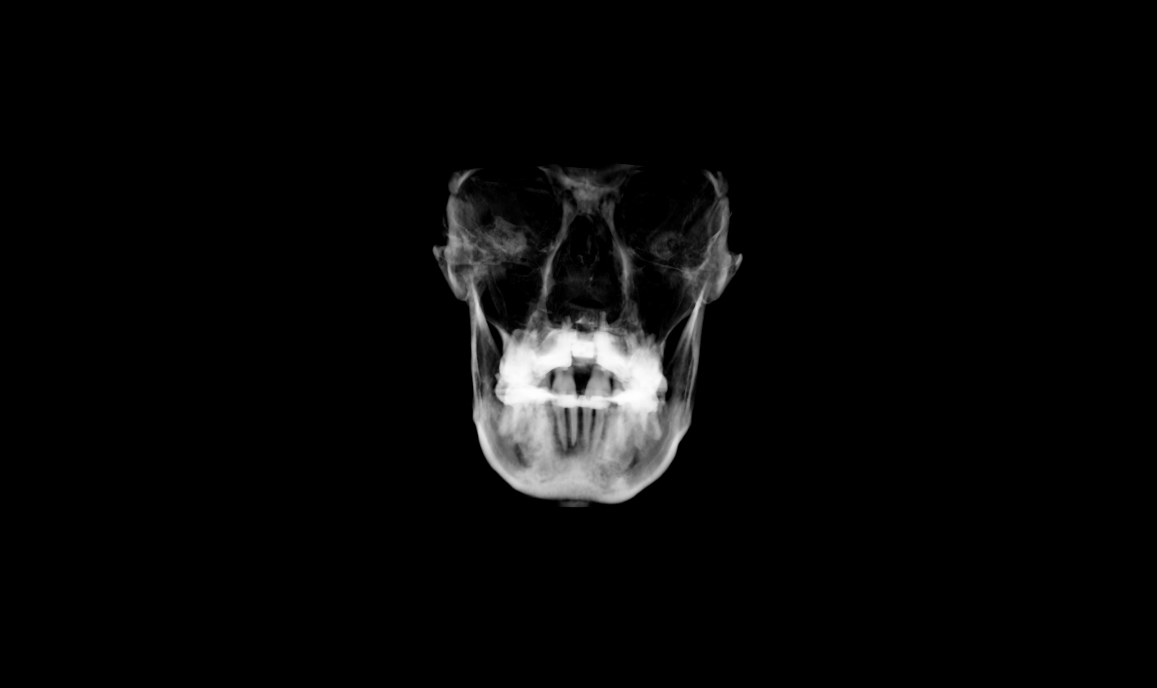

CBCT: